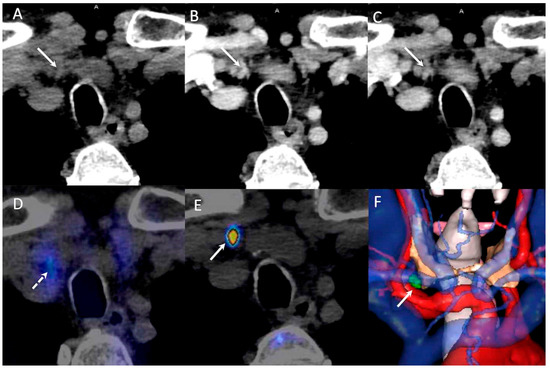

- Piccardo, A.; Trimboli, P.; Rutigliani, M.; Puntoni, M.; Foppiani, L.; Bacigalupo, L.; Crescenzi, A.; Bottoni, G.; Treglia, G.; Paparo, F.; et al. Additional value of integrated 18F-choline PET/4D contrast-enhanced CT in the localization of hyperfunctioning parathyroid glands and correlation with molecular profile. Eur. J. Nucl. Med. Mol. Imaging 2019, 46, 766–775. [Google Scholar] [CrossRef]

- D’Agostino, J.; Diana, M.; Vix, M.; Nicolau, S.; Soler, L.; Bourhala, K.; Hassler, S.; Wu, H.S.; Marescaux, J. Three-dimensional metabolic and radiologic gathered evaluation using VR-RENDER fusion: A novel tool to enhance accuracy in the localization of parathyroid adenomas. World J. Surg. 2013, 37, 1618–1625. [Google Scholar] [CrossRef] [PubMed]